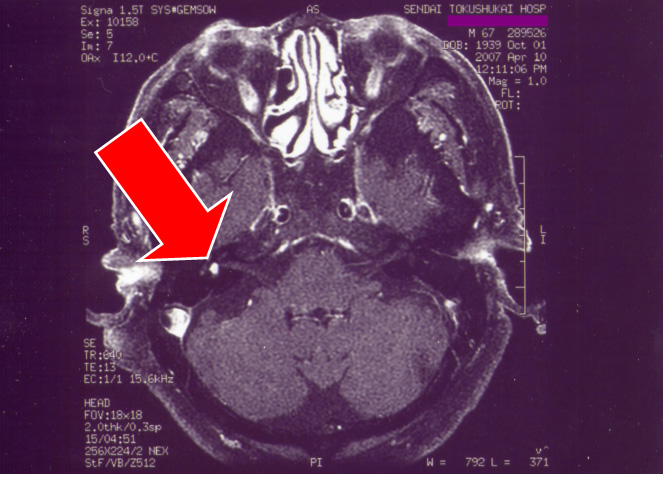

次にMRI画像(図12、13)を示すが、矢印が右側前庭内神経鞘腫である。

図12 図13